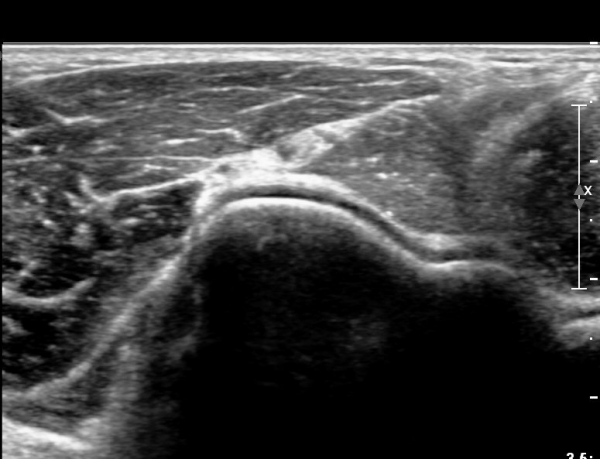

ÆÈ²ÞÄ¡ ¾Õ, Èİñ°£½Å°æ Ⱦ´Ü¸é °Ë»ç¿¡¼ Èİñ°£½Å°æÀÇ ºÎÁ¾ÀÌ °üÂûµÇ°í (»çÁø 1),